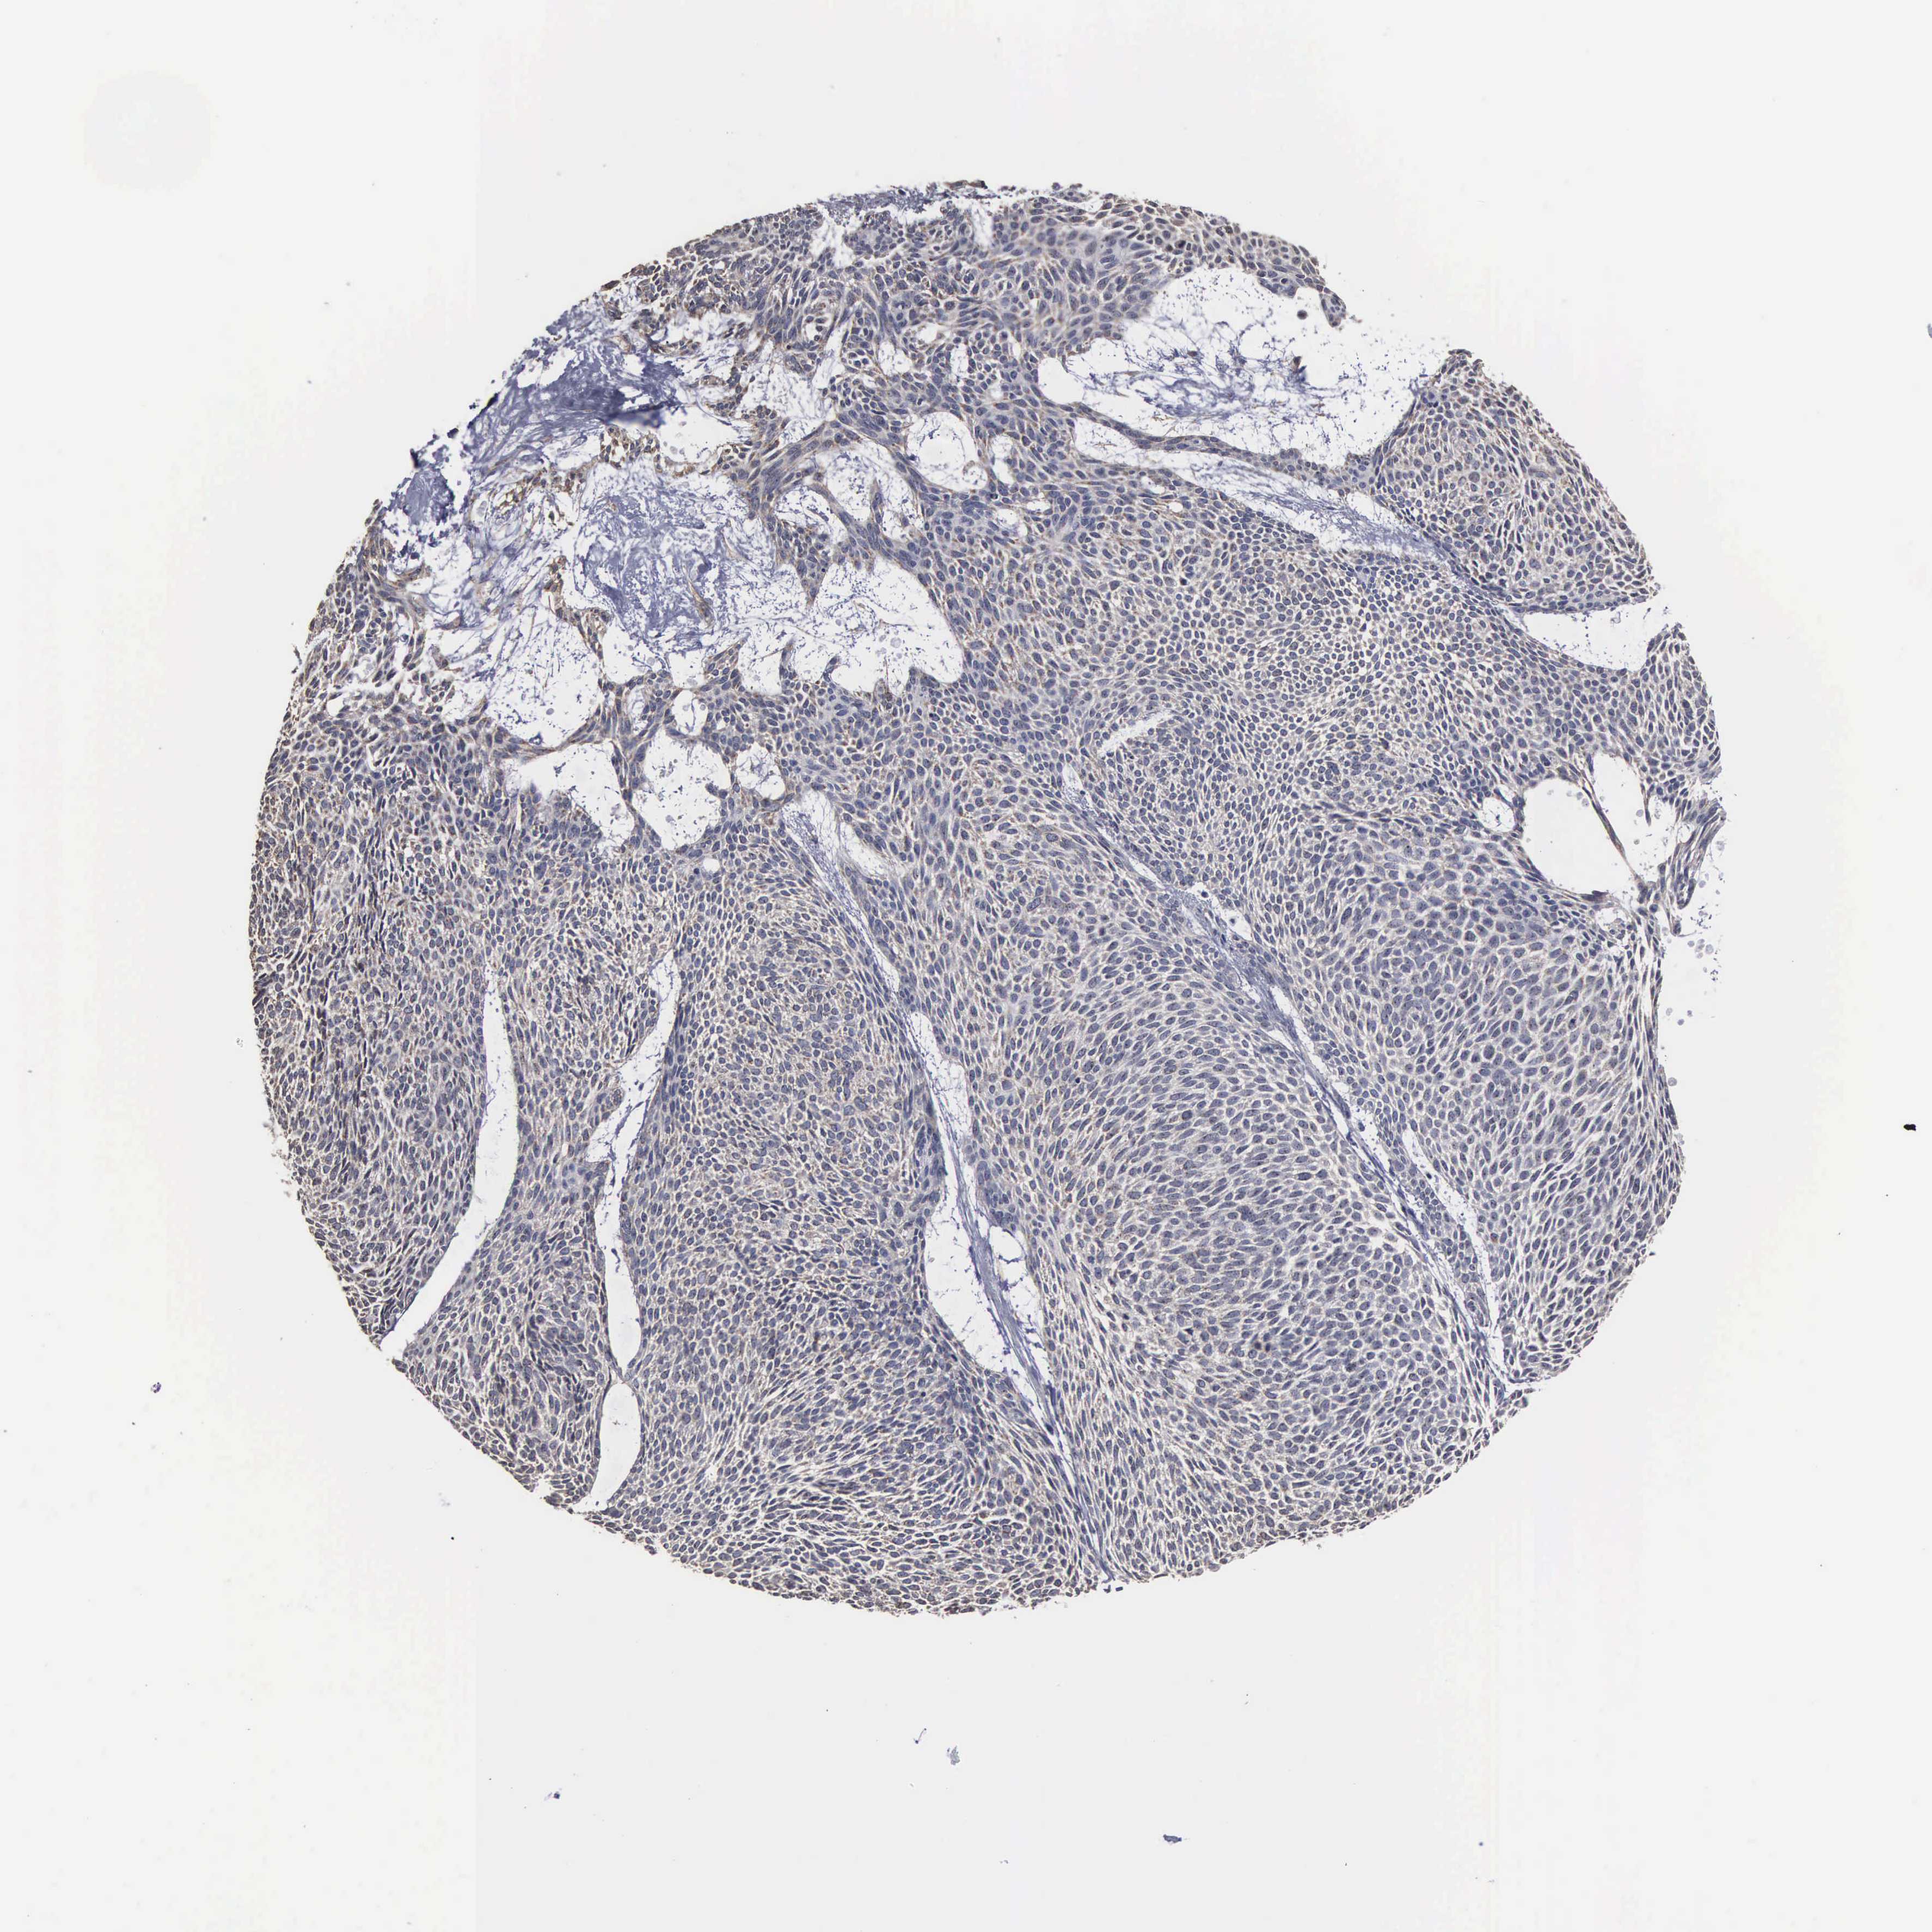

SKIN CANCER - Protein expressioni

A mouse-over function shows sample information and annotation data. Click on an image to view it in a full screen mode. Samples can be filtered based on level of antibody staining by selecting one or several of the following categories: high, medium, low and not detected. The assay and annotation is described here.

Antibody stainingi

Antibody staining in the annotated cell types in the current human tissue is reported as not detected, low, medium, or high, based on conventional immunohistochemistry profiling in selected tissues. This score is based on the combination of the staining intensity and fraction of stained cells.

Each image is clickable and will lead to virtual microscopy that enables deeper exploration of all samples and also displays staining intensity scores, fraction scores and subcellular localization as well as patient and tissue information for each sample.

Antibody HPA000944

Staining

High

Medium

Low

Not detected

Intensity

Strong

Moderate

Weak

Negative

Quantity

>75%

75%-25%

<25%

None

Location

Nuclear

Cytoplasmic/membranous

Cytoplasmic/membranous,nuclear

Squamous cell carcinoma, NOS

Basal cell carcinoma